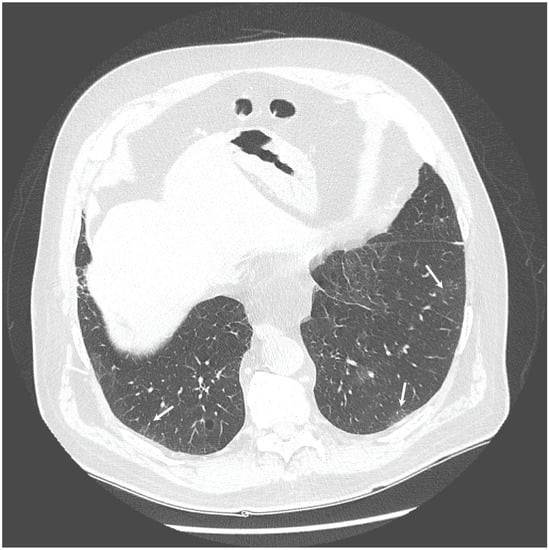

The chest X-ray showed linear opacities in the lower right lobe due to atelectasis, comparable to the previous examination results. The high-resolution computed tomography confirmed emphysema features and revealed thickening of bronchial walls with secretions accumulation and slight post-inflammatory changes (Figure 1 and Figure 2). No features of bronchiectasis nor enlarged lymph nodes in mediastinum and hilar space were present, and no fluid signs in the pleura.

Figure 1. HRCT scan—Emphysema—the white arrow indicates the emphysematous changes in the lung.